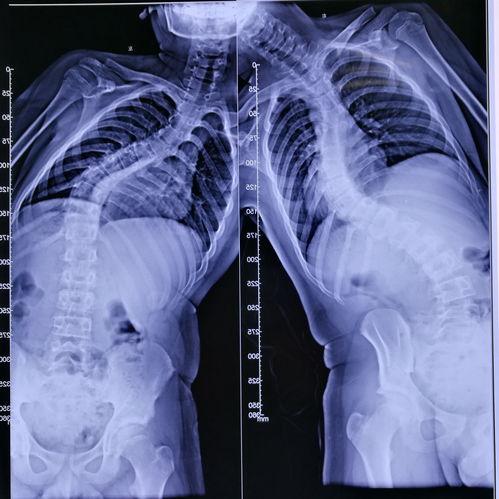

首先,让我们来了解一下什么是脊柱侧弯。脊柱侧弯,顾名思义,就是脊柱在X光片上呈现出的侧弯状态。这种状况可能会影响一个人的外观、姿势,甚至呼吸。据统计,全球约有3%的人患有脊柱侧弯,其中女性患者多于男性。